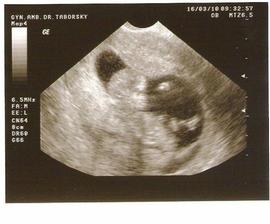

● 16.3 11+2tt vše je v pořádku miminko se krásně hýbalo až musel p. dr. nastavit si monitor aby ho hezky vyfotil, tolik mrskalo ručičkama i nožkama no krása fotečka je uplně úžasná 🙂, další ko za 3 týdny 6.4. ještě 24.3 jdeme na NT+screening tak snad i tam vyjde vše v pořádku 😀 mimi má 5cm od hlavičky po zadeček